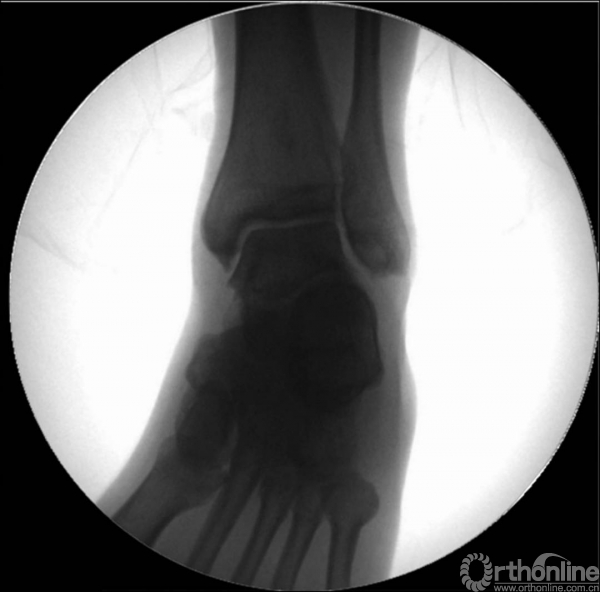

X线诊断:标准的踝关节影像学评估应包括3个位相:前后位(图5),踝穴位(内旋15°)(图6),侧位(图7)。

图6 踝穴位(内旋15°)

当踝关节严重损伤时内外踝及距骨将发生不同程度的移位(图8)。有时外踝骨折会伴有三角韧带的损伤,静态的X线摄片并不能准确地反映踝关节的稳定性,应力位片及MRI检查可完善对踝关节稳定性及韧带损伤的评估(图9)。此时应通过患肢损伤机制及放射资料准确判断踝关节损伤的类型以正确指导复位和固定。有时单纯内踝骨折可能是更为复杂的“Maisonneuve骨折”的一部分,该骨折还包括腓骨近端骨折及韧带联合损伤,故X线检查应投照整个胫腓骨。

图9 应力位X线片(三角韧带断裂)